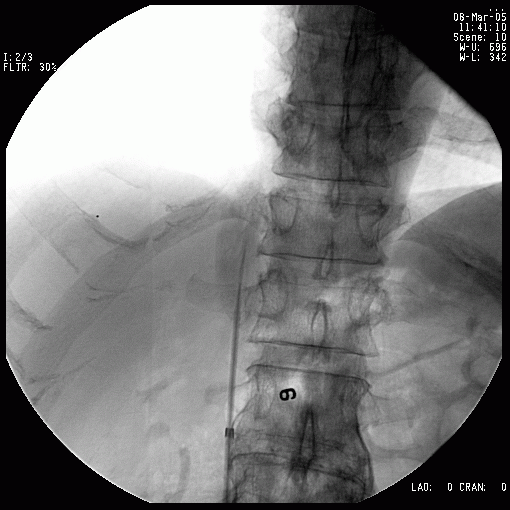

病例二 (美国巴德滤器)

图B: 过滤器植入前定位。